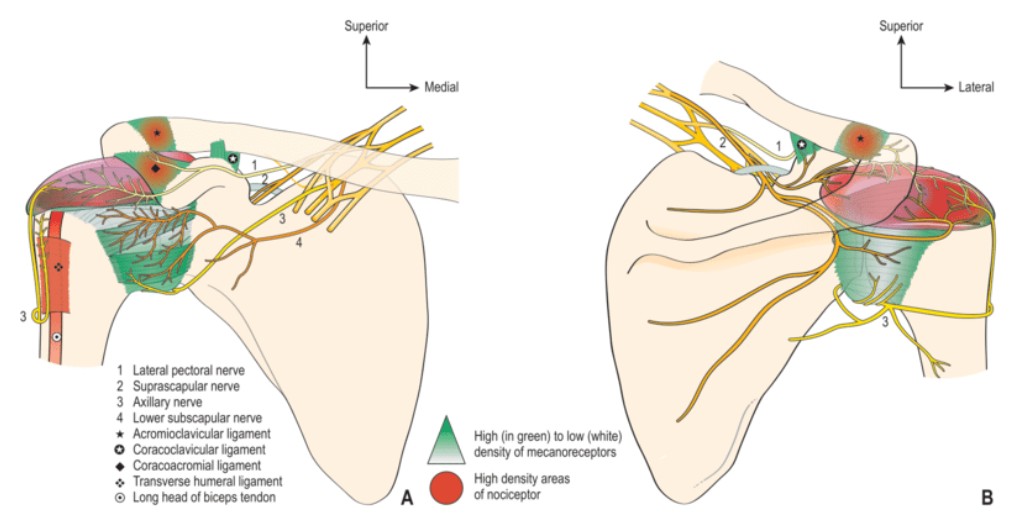

根據神經感覺支配位置精準阻斷

插圖來源:Sensory innervation of the human shoulder joint: the three bridges to break. Laumonerie, Pierre et al. Journal of Shoulder and Elbow Surgery, Volume 29, Issue 12, e499 – e507